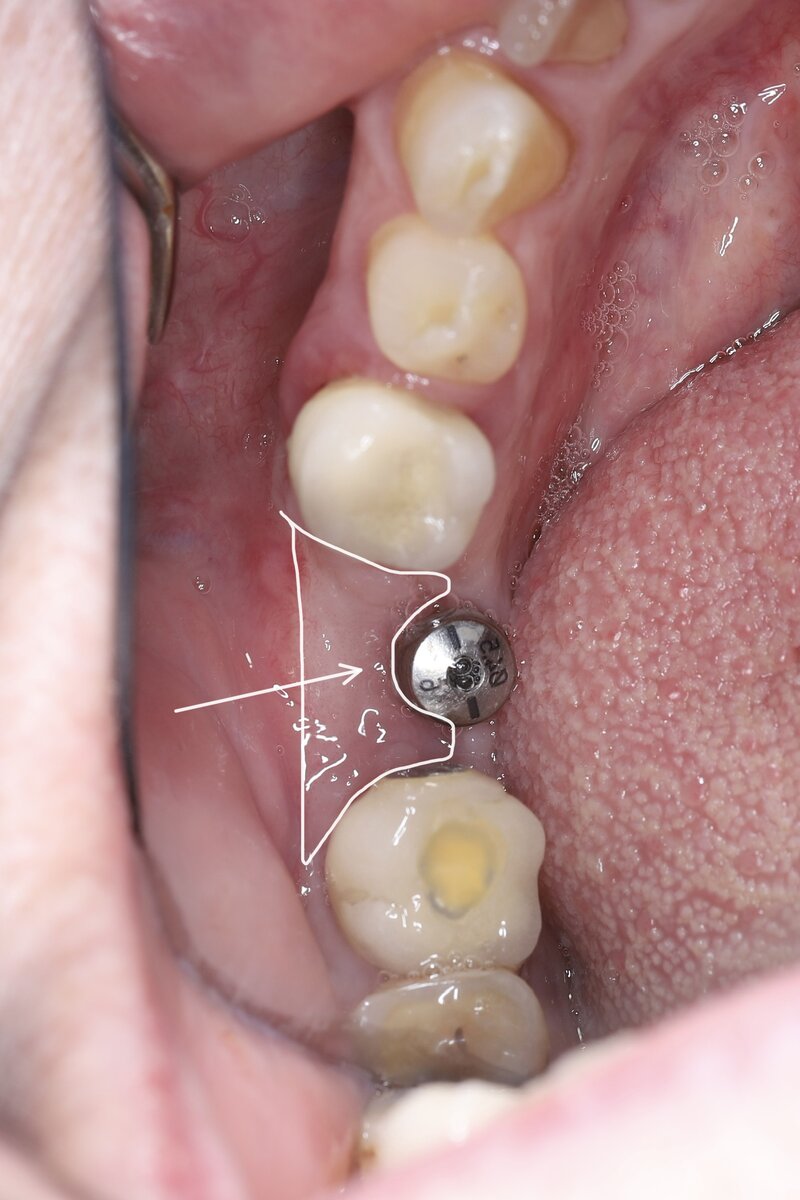

Осложнения имплантологического лечения. Десневая пластика в области имплантата.

Когда - то давно был установлен имплантат и установили спаянные коронки. Потом начала забиваться пища под коронку на 6 имплантате снизу и это вызывало чувство дискомфорта и неприятные ощущения. Потом десна стала красного цвета, отёчна и набухла.

Пациент попал ко мне на консультацию. Сделали снимки. Я увидел очаг разряжения костной ткани вокруг имплантата, характерный для периимплантита (воспаление вокруг имплантата).

Отсутствие десны является большой проблемой для установленных имплантатов, так как подвижная десна постоянно, как насос, качает и забрасывает пищу в это пространство. В итоге в этом месте оседает пища, она там начинает гнить и подлежащая костная ткань и десна атрофируется (убывает).

Результат до и после:

Воссозданный объём:

Воссозданный объём вид сбоку: